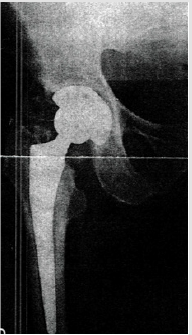

Male patient with 83 years of age, with history of total hip replacement 3 years ago, presenting HO Brooker III of the ipsilateral hip (Figure 1). He presented with pain and claudication. He underwent a single fraction of 750 cGy few hours before revision of the arthroplasty with substitution of the prosthesis on July of 2015. A 2D planning was done with AP-PA field toward the entire coxo-femoral joint (Figure 2). Treatment delivery was done on linear accelerator with photon energy of 18MV. Following treatment, patient experienced a significant improvement of his condition, with decrease on pain and regains the ability to do his daily activities by his own. On a radiograph taken 6 months after radiotherapy and surgery there are no signs of HO (Figure 3). Unfortunately he passed away three years later (July of 2018) of a mesothelioma diagnosed in 2017.

Male patient with 67 years of age, with previous total hip replacement 7 months ago. His comorbidities were osteoporosis, heart valve replacement and diabetes induced kidney injury. One month after surgery his radiograph showed smoldering signs of HO (Brooker I/II – Figure 4). Patient gradually developed pain, which got worse with time and decrease joint motion with progressively inability to flexion and elevation of the leg. On the control radiograph taken 5 months after surgery there were signs of HO Brooker III (Figure 5) and patient became more symptomatic with pain level 10 out a scale of 10. He presented to our department on February 2019 with functional impairment, depression, pain and inability to perform his daily activities like driving. We performed a CT simulation on supine positioning, followed by a 3D conformal RT planning and treatment was delivered with a single fraction of 800 cGy on linear accelerator using photon energy of 18MV covering the entire joint (Figure 6). On the follow-up visit, one month after treatment, patient showed a decrease on his pain level (from 10 it decrease to 5 out a scale of 10) and regain some level of joint motion that allowed him to drive again and do some of his life activities.